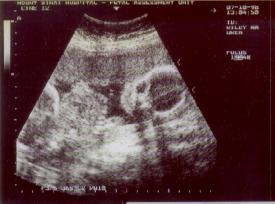

Diana, the nurse, said she would do a quick ultrasound to show us

all was okay. Now I had asked for an image the last 2 visits, but something

came up each time, and the nurse ended up having more important things

to do. But this time, with things a little more relaxed, she was able to

"click" off the below pictures:

Abigail

&

Boris

What you are seeing, is the head of each of the babies. With Abigail,

it is easier to see her body extending off to the left! But in both cases,

it looks like they are wearing Halloween masks!